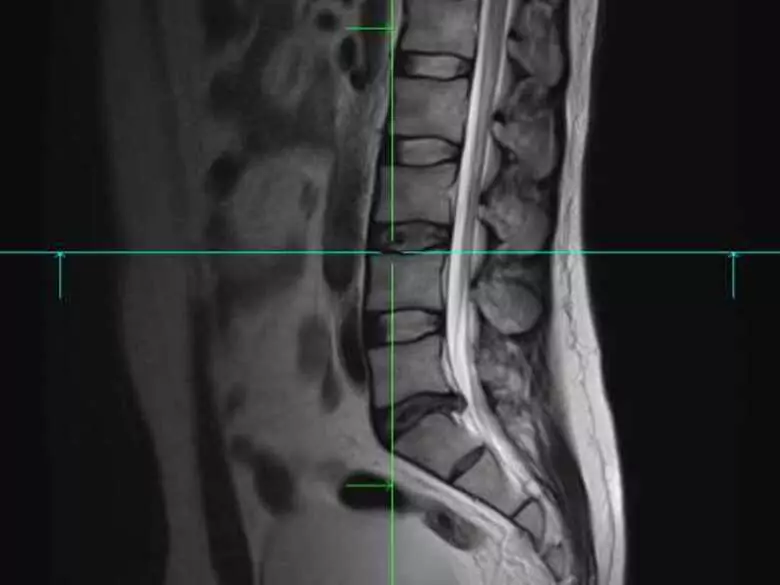

Une discopathie n'est rien d'autre que le prolapsus d'un disque intervertébral hors de sa place, de sa position naturelle. Dans la plupart des cas, les discopathies touchent la partie inférieure de la colonne vertébrale (segments sacrés et lombaires).